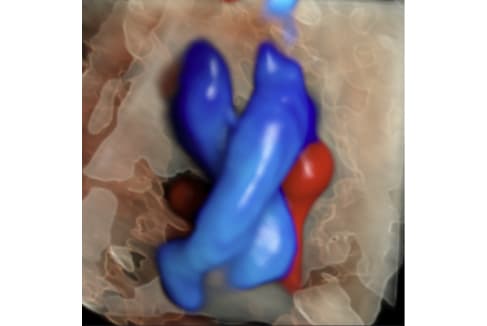

- 4D STIC Fetal echocardiography and Fetal Quantification ( fetal HQ analysis)

- Most advanced technology- including Voluson Expert 22 Ultrasound equipment with its full array of transducers and fetal HQ software- for fetal heart function assessment.

- Accurate diagnosis of fetal heart defects through real-time and offline analysis of fetal heart function evaluations.